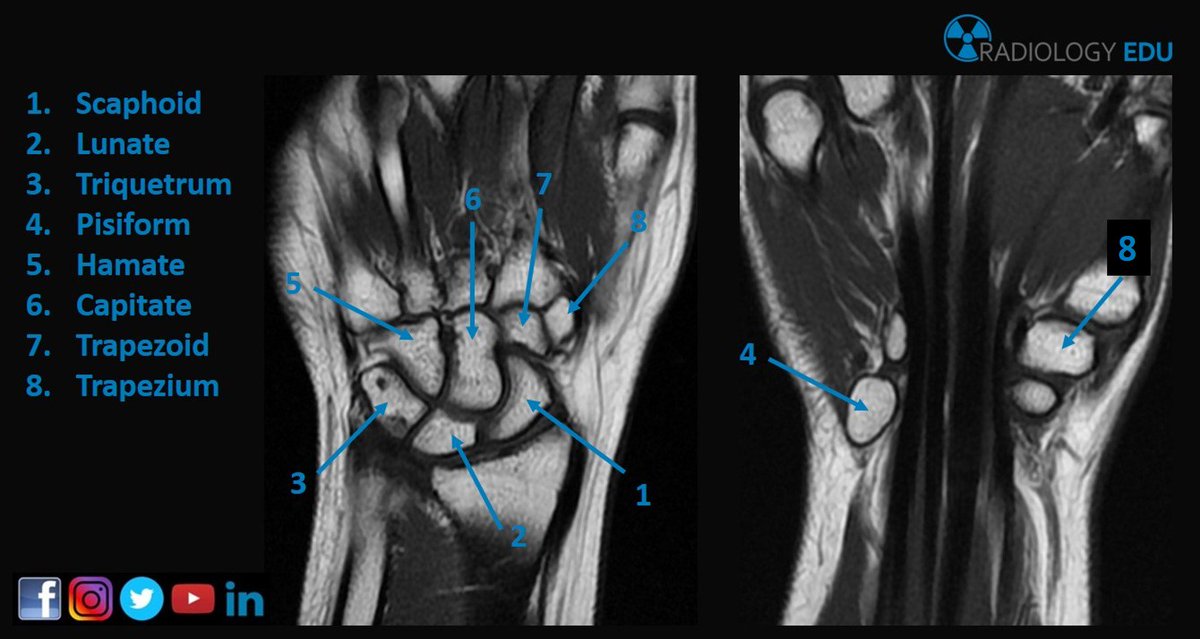

Carpal Bones Radiograph Labeled - Carpal Bones Mnemonic Anatomy Nursing And Medical Notes Basic Anatomy And Physiology Human Anatomy And Physiology Medical Knowledge : Carpi), are the eight bones of the wrist that form the articulation of the forearm with the hand.. The normal carpal bone angles were determined using the bone axes with the least observer variability (mean and range): Proximal row scaphoid lunate triquetrum pisiform. Swipe right for the answers! Start studying carpal bones labeling anatomy. The other four, superior or brachial, inferior or metacarpal , external or.

Carpi), are the eight bones of the wrist that form the articulation of the forearm with the hand. The term carpus is derived from the latin carpus and the greek καρπός (karpós). Triangular appearance of lunate on frontal projection. Study the carpal bones as pieces of a jigsaw puzzleleft: Capitate and all other carpal bones lie posterior to lunate on lateral radiograph. The carpus is a composite joint composed of all the articulations to which the seven carpal bones contribute. Occurs when the lunate maintains normal position with respect to the distal radius while all other carpal bones are dislocated posteriorly. The carpal bones are the eight small bones that make up the wrist (or carpus) that connects the hand to the forearm. An easy and convenient way to make label is to generate some ideas first. The carpal bones are the eight bones of the wrist that form the articulation of the forearm with the hand. If an abnormal alignment of the carpal bones is depicted during imaging of the. Articulates with ulnar carpal bone. Dynamic instability is present if the carpal bones appear normal in standard radiographs taken at rest, but abnormal movement is identified in clinical examination, radiographic stress views, or cineradiography.

I Examination Of The Wrist Surface Anatomy Of The Carpal Bones Sciencedirect from ars.els-cdn.com They are usually divided into two rows: If an abnormal alignment of the carpal bones is depicted during imaging of the. Start studying carpal bones labeling anatomy. (a) distal phalanx 1st digit, (b) interphalangeal joint, (c) proximal phalanx 1st digit. The carpal bones, also known as the carpus (plural: Capitate and all other carpal bones lie posterior to lunate on lateral radiograph. The carpal bones are the eight bones of the wrist that form the articulation of the forearm with the hand. The distal row articulates with the bases of the metacarpal bones forming the pa hand radiograph above have the following structures labeled:

Identify the carpal bones labelled a, b, c, d, … view full text. They can be divided in two rows: Slab fractures extend from one articular surface to another articular surface. Log in through your library. Can you name each of the carpal bones in this radiograph? The carpal bones are the eight bones of the wrist that form the articulation of the forearm with the hand. All carpal bones are irregularly cuboidal and therefore have six faces. Swipe right for the answers! Paired cranial bones of the skull by dr khaled shoghy. Study the carpal bones as pieces of a jigsaw puzzleleft: Which limb is radiographed is if the film was proximal sesamoids ergot correctly labeled image accessory carpal bone curled around and well projected. Each radiograph in this dataset is an image of a left hand labeled with. {label gallery} get some ideas to make labels for bottles, jars, packages, products, boxes or classroom activities for free.